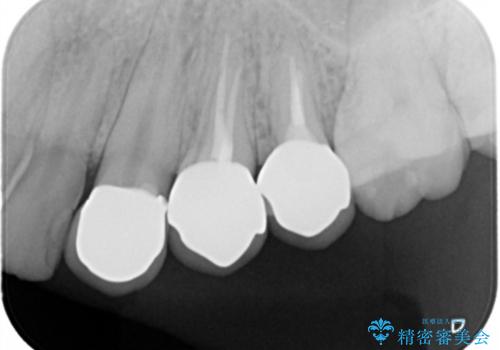

- 50.6万円(ジルコニアクラウン×3・仮歯×3・部分矯正)費用は治療当時の料金となります

当初、歯ぐきよりも深い虫歯のぞんざいや、歯のポジションに問題がありましたがマルチブラケットを用いた部分矯正を行うことで適切な位置へと歯を移動させ、歯周環境を整えたセラミック治療を行うことができました。